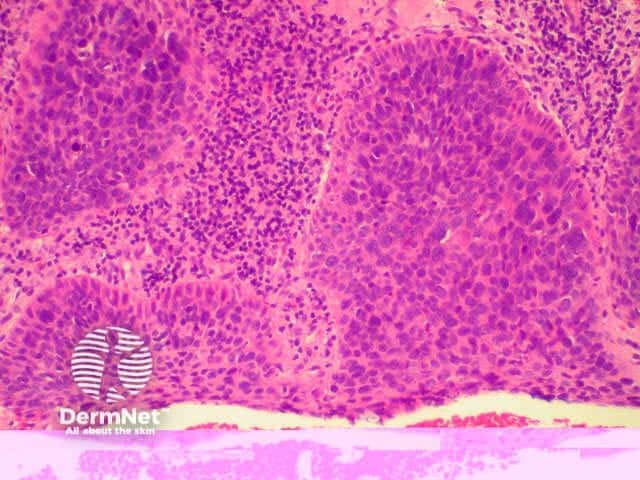

The histological characteristics of keratinocytic tumours are illustrated below.

Actinic keratosis